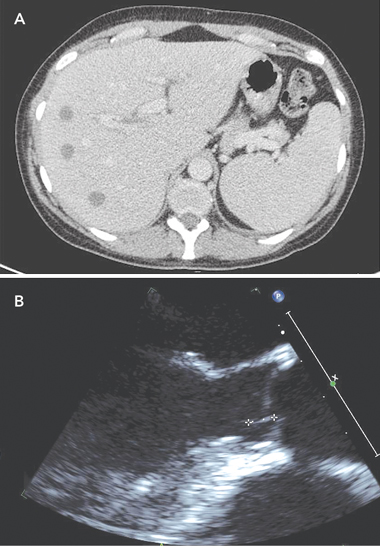

On Day 4, a computed tomography (CT) scan of the abdomen and pelvis showed multiple discrete hypodense lesions measuring up to 1.7 cm throughout the liver, and a bulky spleen (Box 1, A). Deep-purple and black colonies grew on Mueller–Hinton blood agar and antibiotic sensitivity plates. Chromobacterium violaceum, sensitive to ciprofloxacin, meropenem and co-trimoxazole, but resistant to gentamicin, was identified, and confirmed by testing on the VITEK 2 system (bioMérieux, Durham, NC, USA). B. pseudomallei, the causative organism of melioidosis,1 is not usually pigmented. The patient was commenced on intravenous meropenem.

Abatement of symptoms was slow, but the patient’s CRP level fell to 17 mg/L on Day 13. A repeat CT scan of the abdomen and pelvis on Day 10 showed generalised reduction in size of the liver abscesses. A transthoracic echocardiogram on Day 11 revealed mild mitral regurgitation. A contrast CT brain scan performed on Day 13 showed no abnormalities. A transoesophageal echocardiogram (TOE) performed on Day 15 demonstrated a small, 8 mm × 1 mm, linear mobile echodensity arising from the left ventricular outflow tract between the commissures of the left and right coronary cusps, consistent with a small vegetation (Box 1, B). An electrocardiogram was normal.